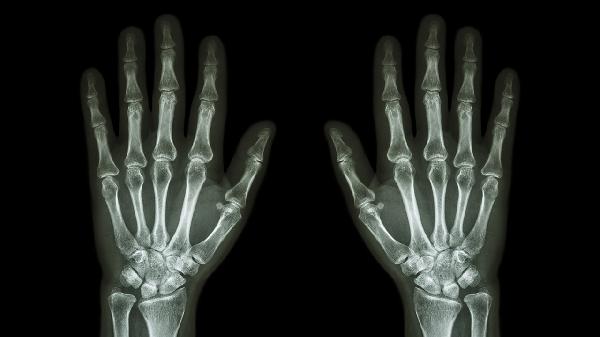

日常应保持手指温暖干燥,冬季外出佩戴保暖手套。饮食注意补充优质蛋白和维生素D,限制高嘌呤食物摄入。建议每周进行3次手指操训练,用温水浸泡后涂抹润肤霜按摩关节。若肿胀持续超过2周或伴随晨僵、畸形等症状,应及时到风湿免疫科就诊,完善类风湿因子、血尿酸、X线等检查。避免自行用力揉搓或过度活动肿胀关节,防止二次损伤。